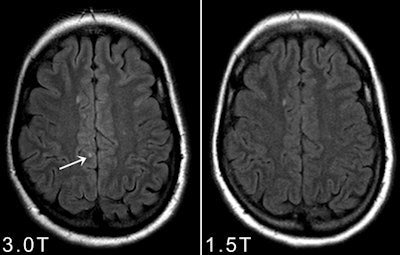

In neuroradiology, the benefits of 3-tesla are quite obvious, not only to obtain better quality routine structural imaging (e.g. of inflammatory lesions), but especially for applications with inherently low SNR, such as susceptibility weighted imaging (SWI), MR angiography (MRA), diffusion tensor imaging (DTI), functional MRI (fMRI), and MR spectroscopy. "However, still up for debate is the crucial question of the diagnostic relevance of 3-tesla MRI, or in other words, 'Does 3-tesla MRI lead to a more sensitive (earlier) and/or more specific diagnosis of certain diseases?' " the authors wrote.

"It has been conclusively shown that 3 tesla shows more (small) inflammatory white and gray matter lesions and offers a better visualization of smaller arterial branches on time-of-flight and contrast-enhanced MR angiography. Despite the fact that this might not lead to an earlier diagnosis of multiple sclerosis, or an earlier detection of aneurysm or vessel malformation with significant therapeutic consequence, (neuro)radiologists would opt for the better image quality if this came at the same cost and level of safety, because it makes the reading procedure easier and more reliable," the authors added.